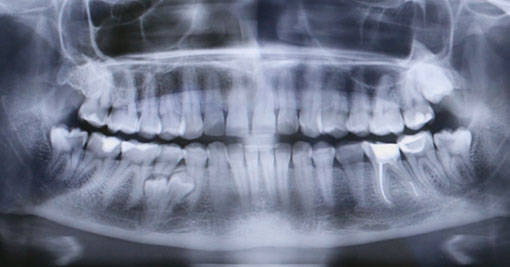

У моей пациентки случайно мы обнаружили два ретинированных сверхкомплектных премоляра:

При этом, весь комплект зубов на месте (за исключением правой верхней восьмерки — моя работа).